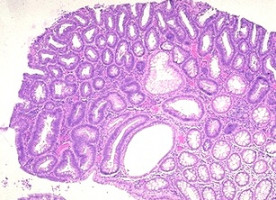

Between 28% and 35% of the U.S. population reported to take dietary supplements containing folic acid, vitamin B6, and vitamin B12, and previous in vitro and animal studies have shown that B vitamins combat colorectal carcinogenesis, and some observational epidemiologic studies suggest a 20%-40% reduced risk in individuals with the highest intake of folate, but most randomized controlled trials have focused exclusively on folic acid supplementation. In order to determine the potential effects of folic acid, vitamin B6 and vitamin B12 on the risk of colorectal adenoma—a precursor to colorectal cancer-- Yiqing Song, M.D., Sc.D., of the Harvard Medical School in Boston and colleagues conducted a study in the Women’s Antioxidant and Folic Acid Cardiovascular Study (WAFACS), a randomized, double-blind, placebo-controlled trial which looked at 5,442 female health professionals who were at high risk for cardiovascular disease. The participants in the WAFACS, which took place between April 1998 and July 2005, were randomly assigned to a combination of folic acid, vitamin B6 and vitamin B12, or placebo. This analysis included 1,470 WAFACS participants who received a follow-up endoscopy at some point during the 9.2-year follow-up period.

The researchers found that the risk of colorectal adenoma among women was not statistically significantly affected by the intake of combined folic acid vitamin B6 and vitamin B12 supplementation. “Our findings do not support recommending B-vitamin supplementation for the prevention of colorectal adenomas,” the researchers write, adding more evidence is needed in order to verify their findings. They also found that consumption of alcohol, known to be a folate “antagonist,” did not influence the effect of supplements on colorectal adenoma risk.